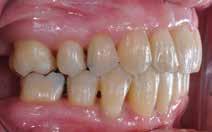

INTRODUKTION OG FORMÅL – Ortodontisk behandling kan være en nødvendighed hos patienter med avanceret parodontitis (stadie 3 og 4), hvis der skal genetableres funktionel okklusion, tilfredsstillende æstetik samt være mulighed for indsættelse af tanderstatninger. Formålet med denne artikel er at præsentere kliniske retningslinjer og en behandlingsmodel for ortodontisk behandling af patienter med velbehandlet parodontitis.

MATERIALE OG METODER – Artiklen bygger på en gennemgang af internationale retningslinjer og kliniske erfaringer, herunder to patienttilfælde, hvor der er foretaget ortodontisk behandling af patienter med stadie 3- og 4-parodontitis. Der beskrives rammer for en systematisk tilgang med fokus på parodontal sundhed, ortodontisk korrektion og livslang vedligeholdelse, hvor hele behandlingen udføres i et tæt interdisciplinært samarbejde.

RESULTATER – Begge patienter opnåede sunde parodontale forhold, funktionel okklusion og forbedret æstetik. Ortodontisk behandling blev iværksat efter opnåelse af parodontal stabilitet og tilpasset det reducerede parodontium med kontrollerede kraftsystemer. Under behandlingen blev parodontiet vedligeholdt, og efter afsluttet ortodontisk behandling blev patienterne fulgt med regelmæssige kontroller af både parodontal sundhed og ortodontisk retention.

KONKLUSION – Ortodontisk behandling af patienter med velbehandlet parodontitis er mulig og kan give gode æstetiske og funktionelle langsigtede resultater med en interdisciplinær tilgang og efterfølgende fokus på vedligeholdelse og retention.

PARODONTITIS kan ubehandlet resultere i ændringer i tandstilling og belastningsforhold, hvilket ofte medfører et behov for ortodontisk behandling. Fra patientens perspektiv vil ønsket om ortodontisk korrektion ofte bero på et ønske om forbedret æstetik (1), mens det fra et tandlægefagligt synspunkt også er muligheden for at opnå en hensigtsmæssig okklusion med bedst mulig kontrol over belastningsforhold, der fører til anbefaling af ortodontisk behandling. Formålet med denne artikel er at præsentere kliniske retningslinjer, der på forsvarlig vis sikrer ortodontisk behandling af patienter med velbehandlet parodontitis.

Vi viser her to ortodontiske behandlinger af patienter med velbehandlet stadie 3- og 4-parodontitis, som begge har tandtab og reduceret, men sundt parodontium, dog med begrundet undtagelse af en enkelt tand, som vi kommer tilbage til. Behandlingerne følger følgende princip:

PATIENTTILFÆLDE 1

Patienttilfælde 1 (Fig. 1) er en 37-årig kvinde, henvist efter succesfuld behandling af stadie 3-parodontitis. Der er nu sundt

Før behandling

parodontium, ingen pocher over 4 mm, og både blødnings- og plakindeks er under 10 %. Patienten er motiveret for ortodontisk behandling, da hendes tænder er vandret over tid, delvist som følge af reduceret parodontium.

Der ses anterior trangstilling i begge kæber og overerupterede 1+1 og 2,1-1,2, hvilket resulterer i dybt bid med 2- tæt på ganepåbidning. Der er normale sidetandsrelationer, men der ses 5 mm horisontalt overbid (HOB) og 7 mm vertikalt

overbid (VOB). Papillen mellem 1+1 er betydeligt reduceret pga. fæstetab, og de mesialt kippede 1+1 har resulteret i en ”dark triangle”. Den facioorale funktion er for nuværende i.a. Panoramarøntgen (Fig. 1, I) viser marginalt knogletab i begge kæber og fravær af 8,7+7,8 og 8,7-8.

Objektivt anbefales behandling af det dybe bid, som ubehandlet forventes at forværres yderligere over tid. Patienten har ønske om behandling med æstetisk ortodontisk apparatur, alignere, og det vurderes muligt at behandle malokklusionen med alignere. Dog anbefales det generelt, at alignere undgås eller benyttes med væsentlige modifikationer af alignerens retention ved tandmobilitet, da dette ellers kan medføre jiggling, når aligneren tages af og på mange gange dagligt. På den anden side er der nogen evidens for, at alignerbehandling er associeret med bedre renhold og parodontal sundhed sammenlignet med fast apparatur (16).

Ortodontisk behandling af patienter med parodontitis kan ofte foretages sikkert ved at følge en systematisk tilgang, der omfatter 1) inflammationskontrol, 2) ortodontisk korrektion og 3) livslang vedligeholdelse. Inden behandlingen påbegyndes, skal parodontiet generelt være sundt med pocher på maksimalt 4 mm og et plak- og blødningsindeks under 10 %. Restfæstet skal være tilstrækkeligt til at modstå behandlingen, som udføres med kontrollerede kraftsystemer. Målet er at forbedre æstetik og opnå normal funktion, som kan vedligeholdes på lang sigt samt facilitere restaurerende behandling.

Der planlægges alignerbehandling af begge kæber med intrusion af 1+1 og 2,1-1,2, nivellering af trangstilling UK med interproksimal reduktion (IPR) (Fig. 2 A, B) og senere IPR OK for reduktion af dark triangles mellem incisiverne efter nivellering. Patienten instrueres i at benytte alignere 20-22 timer/ dag med alignerskift hver 7. dag, og patienten ses hver 3.-8. uge under forløbet. Den første alignerserie består af 16 alignere for nivellering OK/UK og IPR i UK (Fig. 2). Efter denne serie planlægges IPR mellem incisiverne i OK for reduktion af dark triangles (Fig. 3) samt yderligere intrusion af OK og UK-fronten i 12 refinement-alignere. Patienten udviser god kooperation og er meget tilfreds med alignerapparaturet, som er mindre synligt end det faste apparatur (Fig. 4).